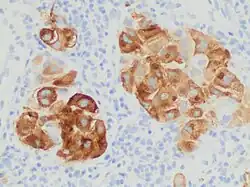

MART-1/melan-A is a protein antigen that is found on the surface of melanocytes. Antibodies against the antigen are used in the medical specialty of anatomic pathology in order to recognize cells of melanocytic differentiation, useful for the diagnosis of a melanoma. The same name is also used to refer to the gene which codes for the antigen.

The MART-1/melan-A antigen is specific for the melanocyte lineage, found in normal skin, the retina, and melanocytes, but not in other normal tissues. It is thus useful as a marker for melanocytic tumors (melanomas) with the caveat that it is normally found in benign nevi as well.